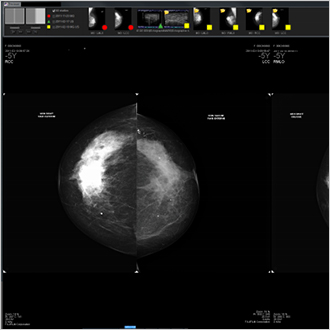

TM-Mammo

De TM-Mammo-oplossing is speciaal ontwikkeld om te voldoen aan de opslag-, distributie- en diagnostische behoeften van alle digitale mammografische beelden die worden gemaakt in de afdelingen voor senologie. Dankzij de TM-Mammo-viewer is vergelijking met eerder gemaakte beeldenreeksen van de patiënt (van alle soorten modaliteiten) eenvoudiger geworden en kan een gebruikersspecifieke weergavesequentie worden gevisualiseerd. Tomosynthese is nu een integraal onderdeel van de weergavesequenties.